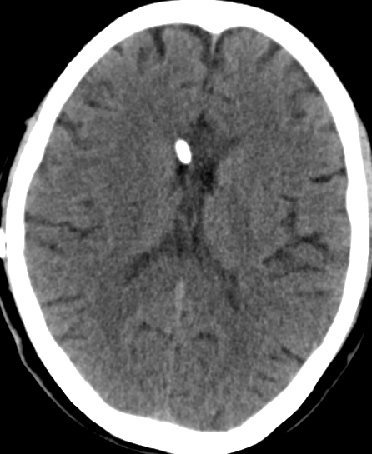

2013-8-12 CT

2013-8-13 调压130——150,头痛症状无明显好转